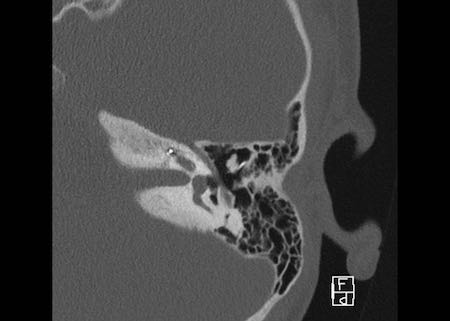

Bên trái là hình ảnh của một bé gái 2 tuổi.

Các hình ảnh từ kết quả chụp CT được thực hiện trước khi cấy ốc tai điện tử.

Quan sát thấy dị dạng nhẹ ở đỉnh ốc tai – không có sự phân tách giữa vòng thứ hai và vòng thứ ba, và trụ ốc tai xương vắng mặt.

Cống tiền đình bình thường.